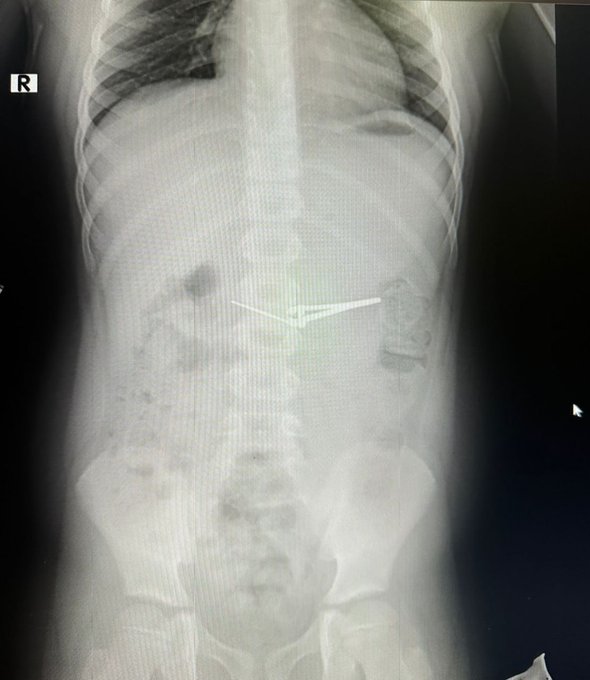

Ребенка с жалобами на боли в животе доставили в детскую больницу № 17. На рентгеновском снимке был отчетливо виден инородный предмет, похожий на складной ножик. По экстренным показаниям мальчику провели лечебную фиброгастроскопию под общим наркозом.

Для извлечения инородного предмета хирурги использовали специальную эндокорзину, что позволило аккуратно захватить и извлечь щипцы, не повредив слизистую оболочку желудка и пищевода. После успешного вмешательства состояние мальчика улучшилось, и через несколько дней его выписали домой с рекомендациями.

фото: t.me/minzdravrb